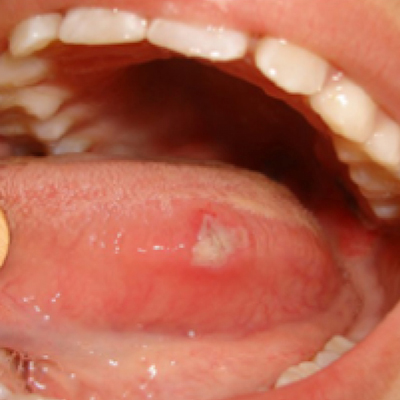

Aftas frequentes ou doloridas?

Fonte: Lopes DN, Marques LC, Rozza-de-Menezes RE, et al. Cytopathological diagnosis of herpes simplex virus infection causing oral aphthous ulcers in a patient with acute lymphocytic leukemia: case report. BMC Oral Health. 2021.